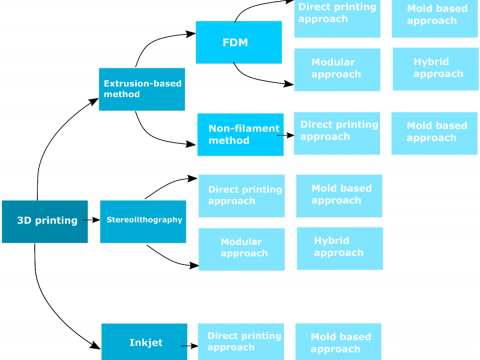

- 3D打印微流控设备:聚焦四种基本制造方法及其对医疗保健领域的影响综述